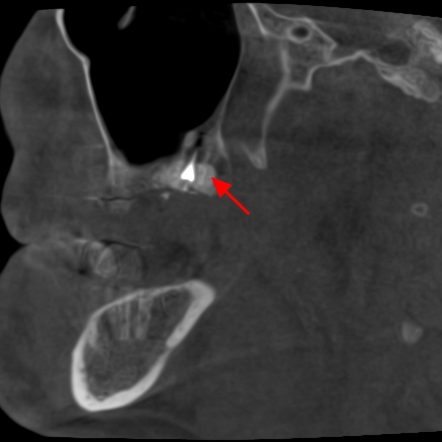

En este contexto, la tomografía computarizada de haz cónico (CBCT) se ha convertido en una herramienta esencial para los profesionales de la odontología. Gracias a la radiología 3D, los especialistas pueden evaluar con exactitud el volumen óseo disponible, identificar estructuras anatómicas importantes (como el nervio dentario o el seno maxilar) y diseñar el tratamiento con la máxima previsión y seguridad.

Para el paciente, esto se traduce en procedimientos más seguros, menos invasivos y con resultados más predecibles. En la fase de seguimiento, el CBCT también permite comprobar la correcta integración del injerto óseo y la evolución del tejido antes de colocar el implante definitivo.